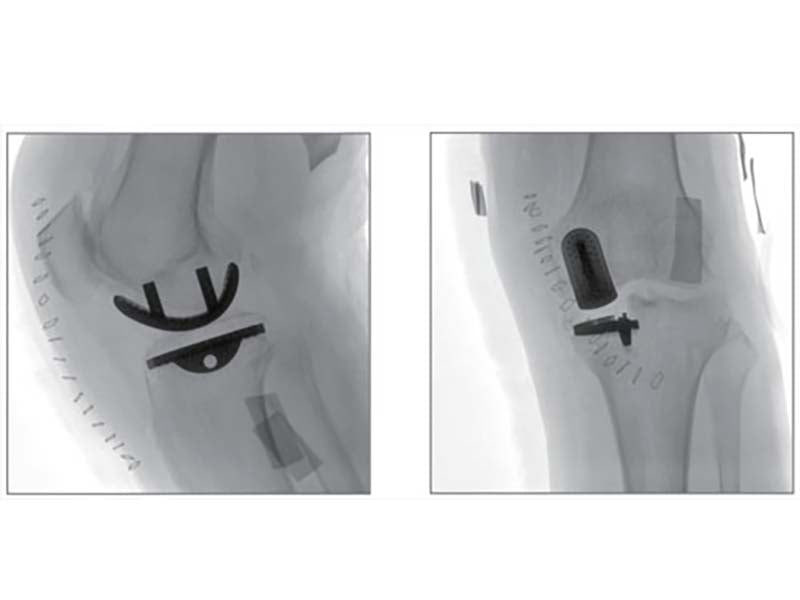

Higher signal coversion efficiency of FPD ensures higher image quality and lower dose.

16 bits depth determines maximum 65536 greyscale value, providing HD resolution for revealing more anatomical details.